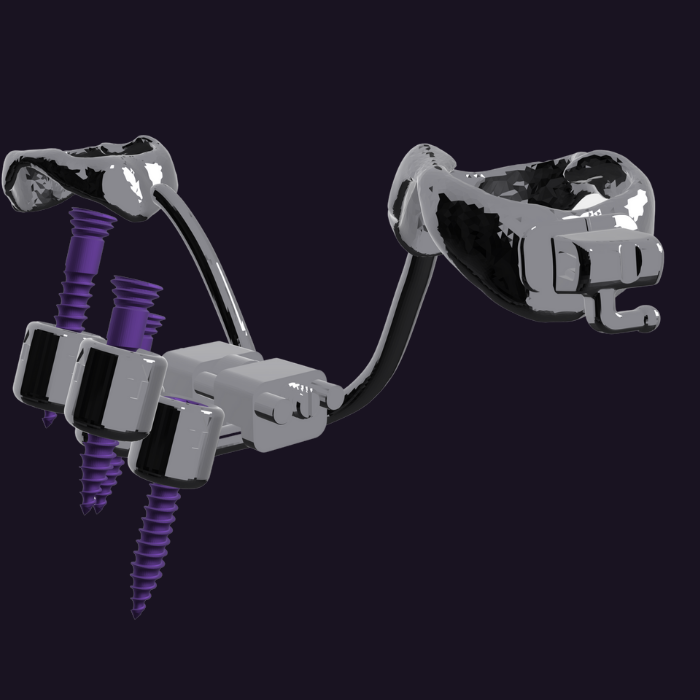

MARPE Sistemi

Mini-Implant Destekli Hızlı Palatal Genişletme

Geleneksel RME sistemlerine göre çok daha üstün sonuçlar sunan, bilimsel olarak kanıtlanmış palatal genişletme yöntemi.

MARPE Aksesuarları

MARPE sistemleri için özel tasarlanmış aksesuarlar ve eklentiler. Ekspansiyon, intrüzyon, distalizasyon gibi ihtiyaç duyulan tüm eklentiler tek sistemde.

- Ekspansiyon eklentileri

- İntrüzyon ve distalizasyon modülleri

- Özel tasarım ve uyum garantisi

- Tak-çıkar yapmadan kol kesimleri ile uygulama